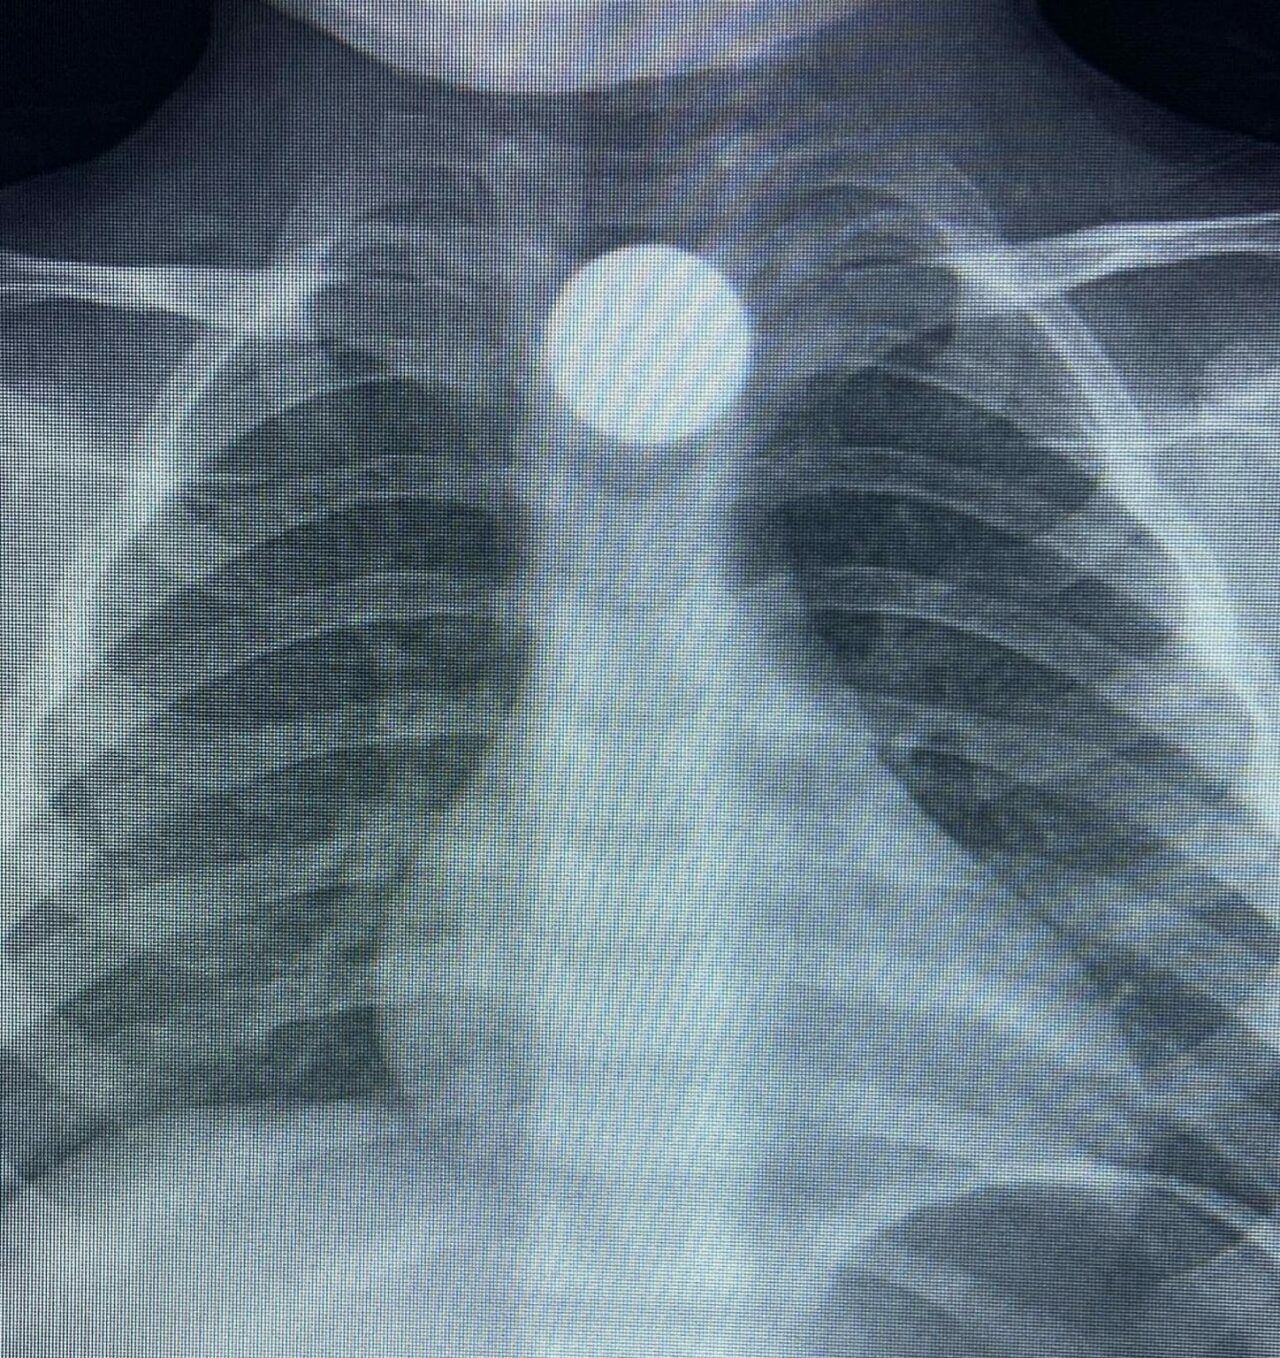

Olay, İnegöl’ün kırsal Yeniceköy Mahallesi’ndeki bir evde meydana geldi. 3 yaşındaki Bilal K., evde yerde bulduğu 50 kuruş madeni parayı ağzına atıp yuttu. Olayı fark eden ailesi tarafından çocuk özel araçla İnegöl Devlet Hastanesi’ne kaldırıldı. Yapılan tetkiklerde yemek borusunda takılı kalan madeni para görüldü. Çocuk ilk tedavinin ardından ambulansla Bursa Yüksek İhtisas Eğitim Ve Araştırma Hastanesi’ne sevk edildi.

Bursa’nın İnegöl ilçesinde madeni para yutan çocuk hastanede tedavi altına alındı. Olay, İnegöl’ün kırsal Yeniceköy Mahallesi’ndeki bir evde meydana geldi. 3 yaşındaki Bilal K., evde yerde bulduğu 50 kuruş madeni parayı ağzına atıp yuttu. Olayı fark eden ailesi tarafından çocuk özel araçla İnegöl Devlet Hastanesi’ne kaldırıldı. Yapılan tetkiklerde yemek borusunda takılı kalan madeni para görüldü. […]